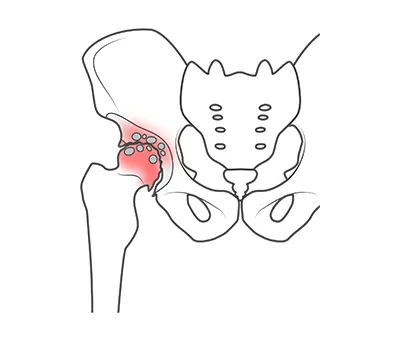

お悩みだった症状

- 腰痛

- 股関節の違和感